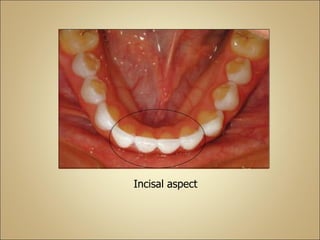

Incisal aspect

●This aspect illustrates the bilateral symmetry of this

tooth.

●The labiolingual diameter is greater than mesiodistal

diameter.

Bilaterally symmetrical

Labiolingually bigger

than mesiodistally